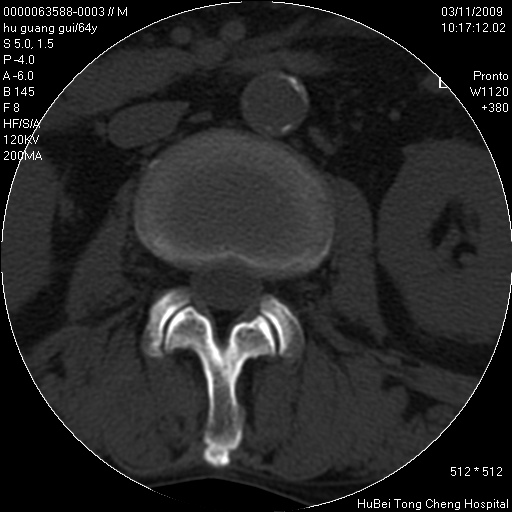

患者 男,64岁。腰痛十余天。(临床未提供其他病史)

临床诊断:腰痛原因待查(腰椎间盘突出症?)。

腰椎间盘ct轴位平扫(层厚5mm,层距4mm),图像如下:

腰椎退行性变,腰4—5椎间盘膨出。

1.腰椎退行性变,腰4—5椎间盘膨出。

1)腰椎退行性变,l4—5椎间盘膨出。2)骶骨右侧块骨转移瘤可能,3)水平骶椎。建议作一步检查。